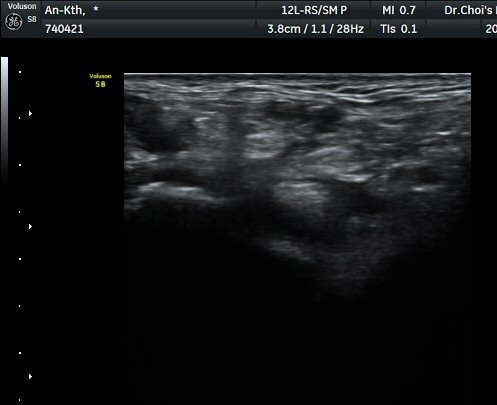

ÃÊÀ½ÆÄ ¼Ò°ß

¹ß¸ñ ³»Ãø Ⱦ´Ü¸é°Ë»ç¿¡¼­ ±ä¾öÁö±¼°î°Ç(FHL)ÀÇ ºÎÁ¾°ú °Ç ÁÖÀ§ ¼ö¾×Àú·ù°¡

°üÂûµÈ´Ù(±×¸² 1, 2, 3). ±ä¾öÀÚ±¼°î°Ç Á¾´Ü¸é°Ë»ç¿¡¼­ ±ä¾öÁö±¼°î°ÇÀÇ ºÎÁ¾°ú